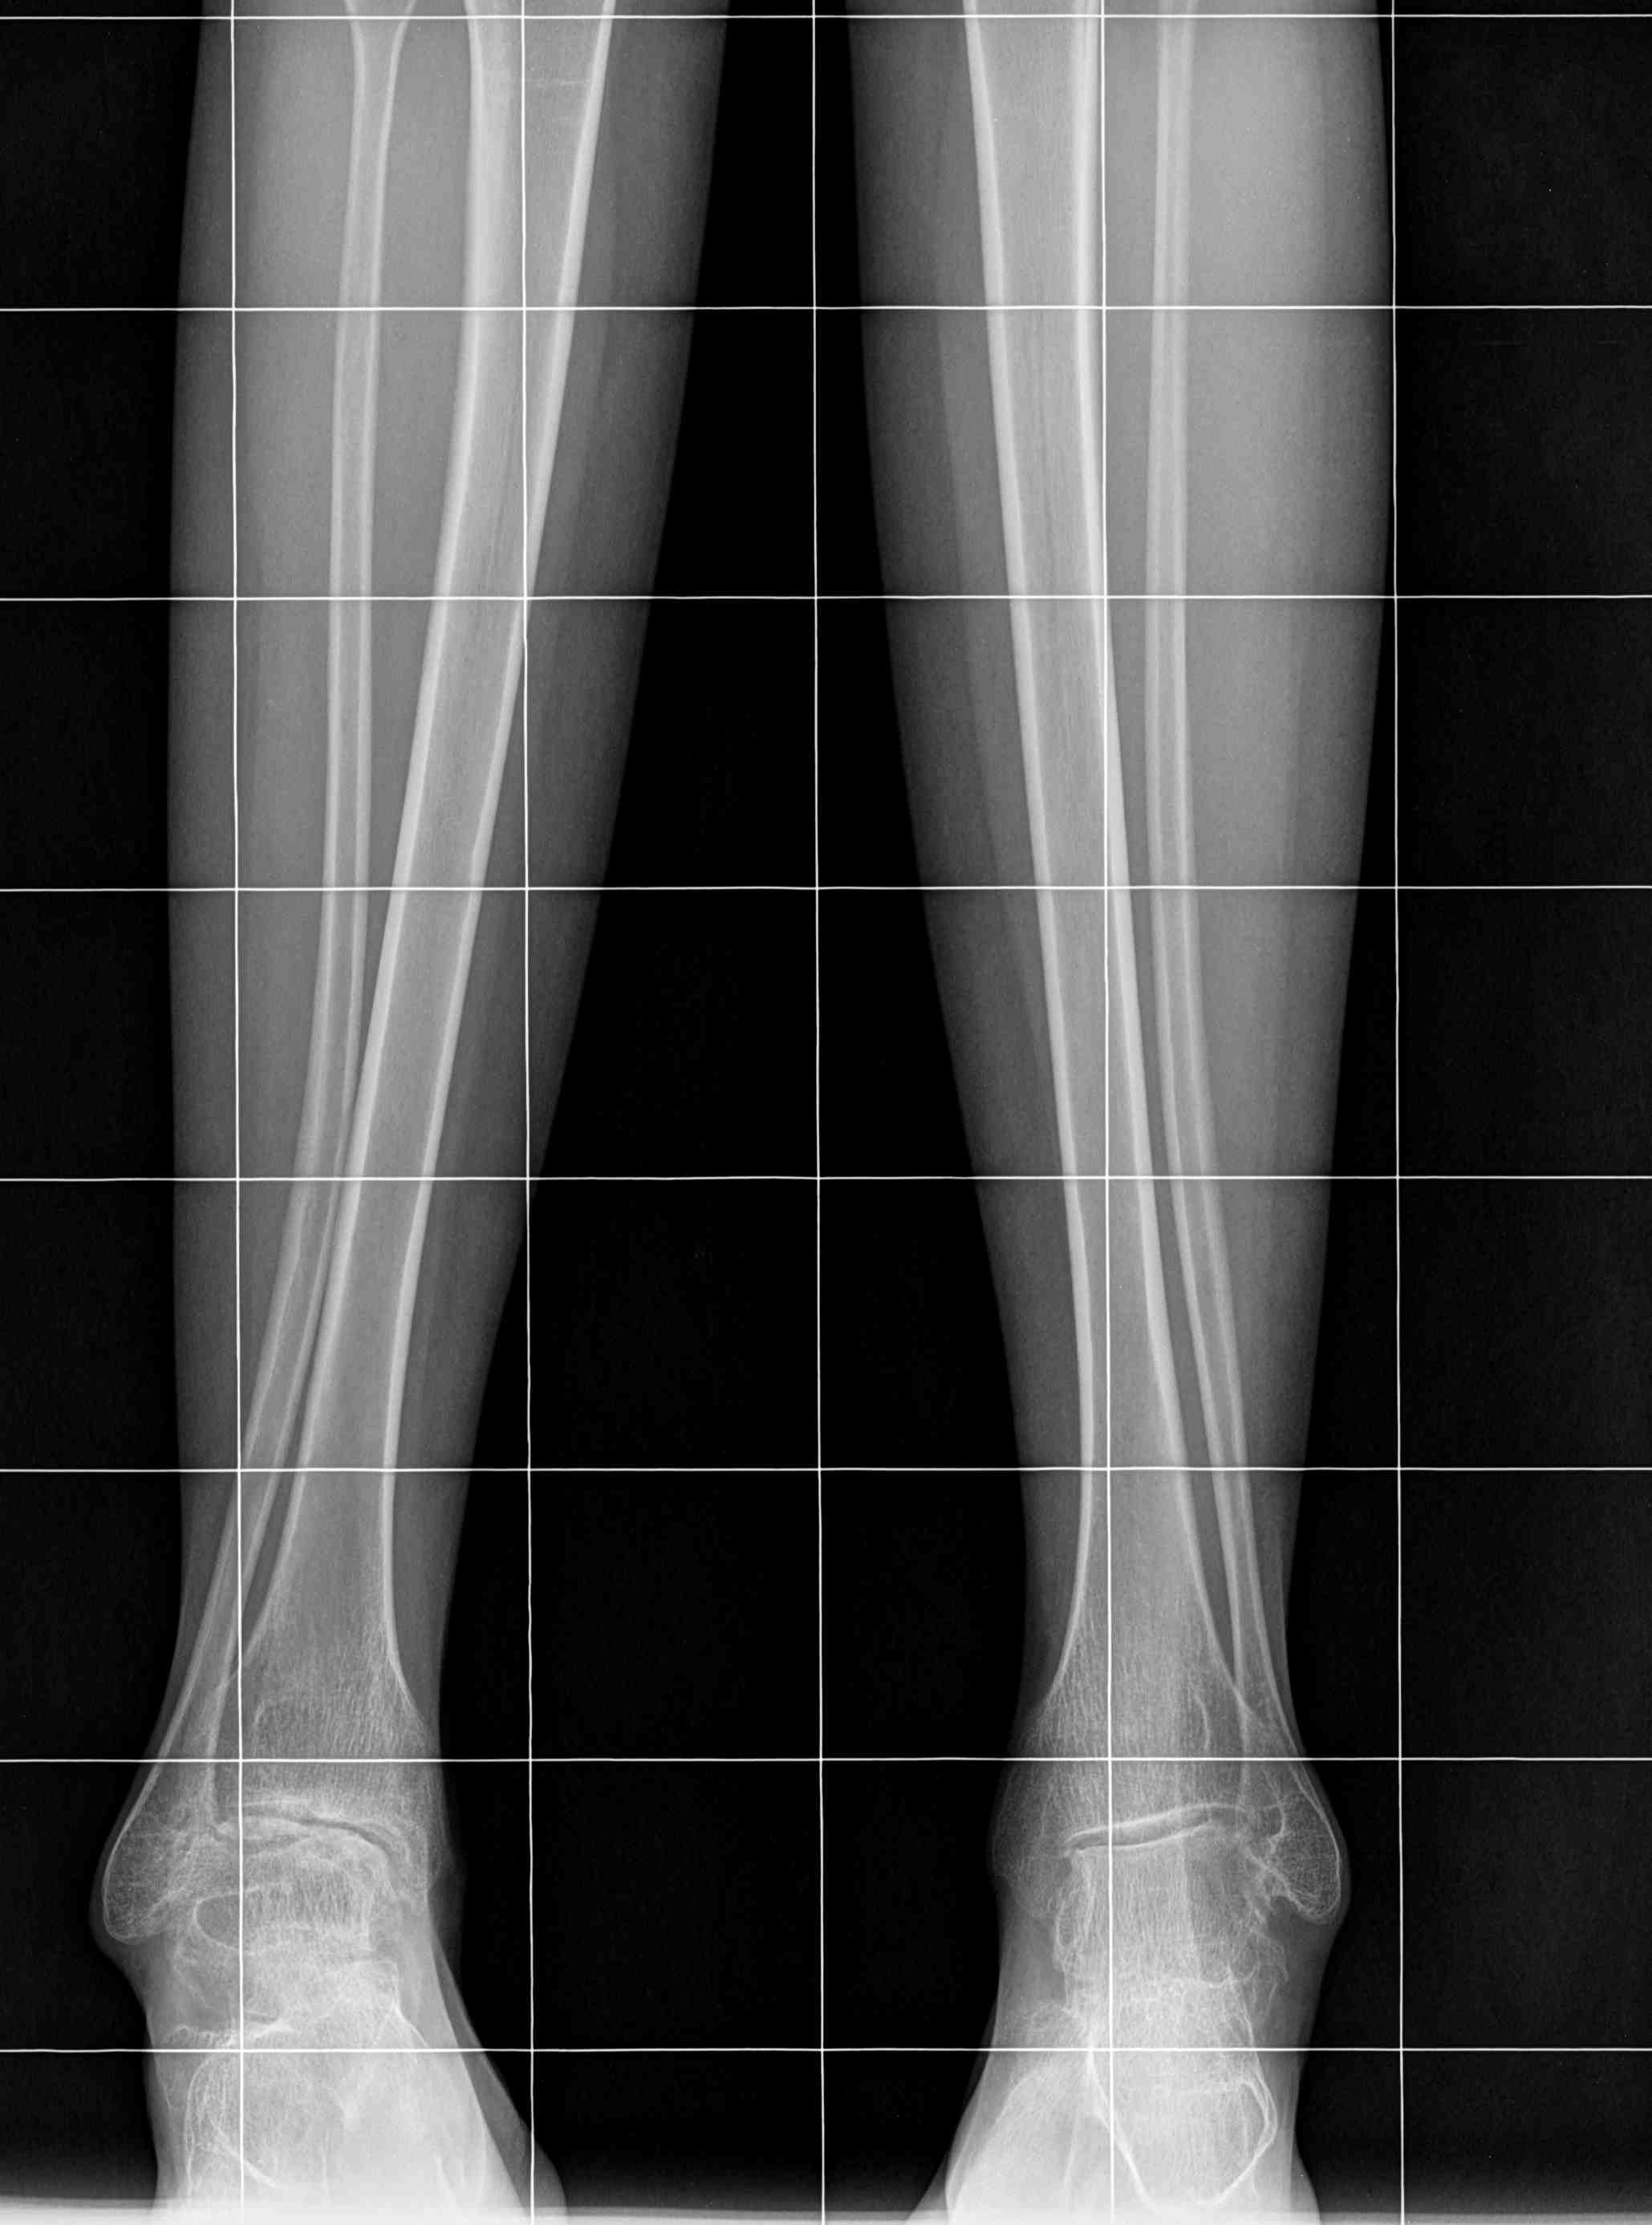

девушка 29 лет с ревматоидным артритом, социальная, лечение получает. вальгусную деформацию на уровне коленных суставов замечает около 10 лет, прогрессирует. Движения в правом коленном суставе:разгибание полное, сгибание около 95-100 град. Боли особой нет. Консультировалась в нескольких НИИ, рекомендовали эндопротезирование.У меня есть желание (вполне, возможно, что и глупое) за сустав "побороться", учитывая возраст, да и первичное протезирование будет не слишком простым. Может исправить деформацию, а там куда кривая судьбы заведет? больше беспокоит боль в голеностопе. В связи с этим есть несколько вопросов: 1. имеет смысл с этим заморачиваться? 2. если да, то в каком объеме? 3. может имеет смысл сделать коррекцию ниже метафиза с одномоментной фиксацией "приличным"гвоздем? Схема прилагается 4. насколько стоит опасаться тракционной нейропатии, стоит сделать острое укорочение или тянуть аппаратом? 5 . еще ряд вопросов, которые я не учел PS книгa Dror Paley пока утеряна вместе с жестким диском, потому не судите строго за дилетанство и приветствуются ваши схемы. Всем большое спасибо за понимание.

Сделаете остеотомию большеберцовой - стопа, которая уже приспособилась к нынешнему положению, повернется кнутри и может утратить контакт с опорой. Голеностопный сустав с признаками выраженной артропатии, скорее всего тугоподвижный. Приспособиться к новому положению не сможет. Значит нужно сразу продумывать последовательность действий, включающую надлодыжечную остеотомию голени или артродез голеностопного сустава (Вам проще оценить его функцию, только по снимку не скажешь). Тем более Вы пишете, что больше беспокоит голеностопный сустав. В этом случае, особенно если думать о надлодыжечной остеотомии, гвоздь может не подойти. А для остеотомий есть хорошие пластины и отработанные техники. С другой стороны, подобное вмешательство можно разбить и на два этапа. Потому что рассчитать все сразу очень сложно. Например, сначала сделать проксимальную остеотомию. Посмотреть, где оказалась стопа и после этого выровнять ее. Но и в этом случае фиксация гвоздем не лучшее решение. Если только не ухитритесь все сделать на одном гвозде. В следующий раз пришлю снимки похожего случая, который делал в 2 этапа.

Максим. Если бы мы вдруг захотели это делать, то остеотомия была бы высокая (над бугристостью). Малоберцовка остаётся интактной. Правда на гвозде не закрепить, но есть пластины

Какую бы не выбрали остеотомию. Выводить ось в ноль я бы не стал. Ориентиром может быть наклон щели голнностопа.

Если пока еще перевариваете, то обдумайте и вариант аппаратного лечения. Все-таки рассчитать все точно под пластину сложно, а аппарат дает возможность внести коррекцию по ходу, уже увидев что куда смотрит под нагрузкой.

Коленный сустав в итоге надо будет протезировать. За что Вы там собрались бороться? Заболевание воспалительное и захватывает весь сустав, а не только его латеральный отдел. Очевидна варусная установка стопы, что можно попробовать устранить клиновидной остеотомией таранной кости и, возможно, артродезом